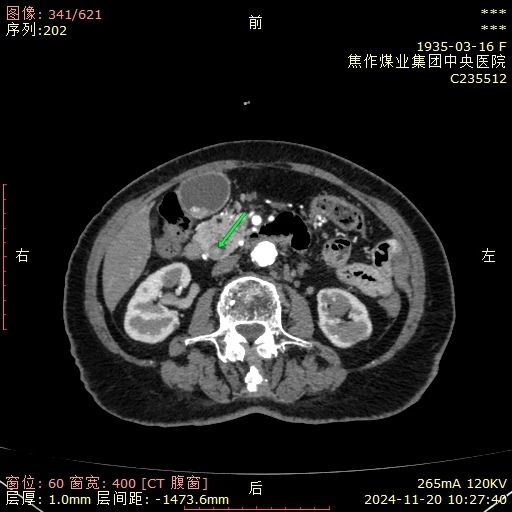

近日,中央医院普通外科一区(肝胆肛肠外科)么甲超团队为一位90岁高龄且腹部四次手术史的女性患者顺利完成腹腔镜下胆囊切除+腹腔镜-胆道镜联合胆管探查取石术,成功为其解除病痛,术后恢 ...